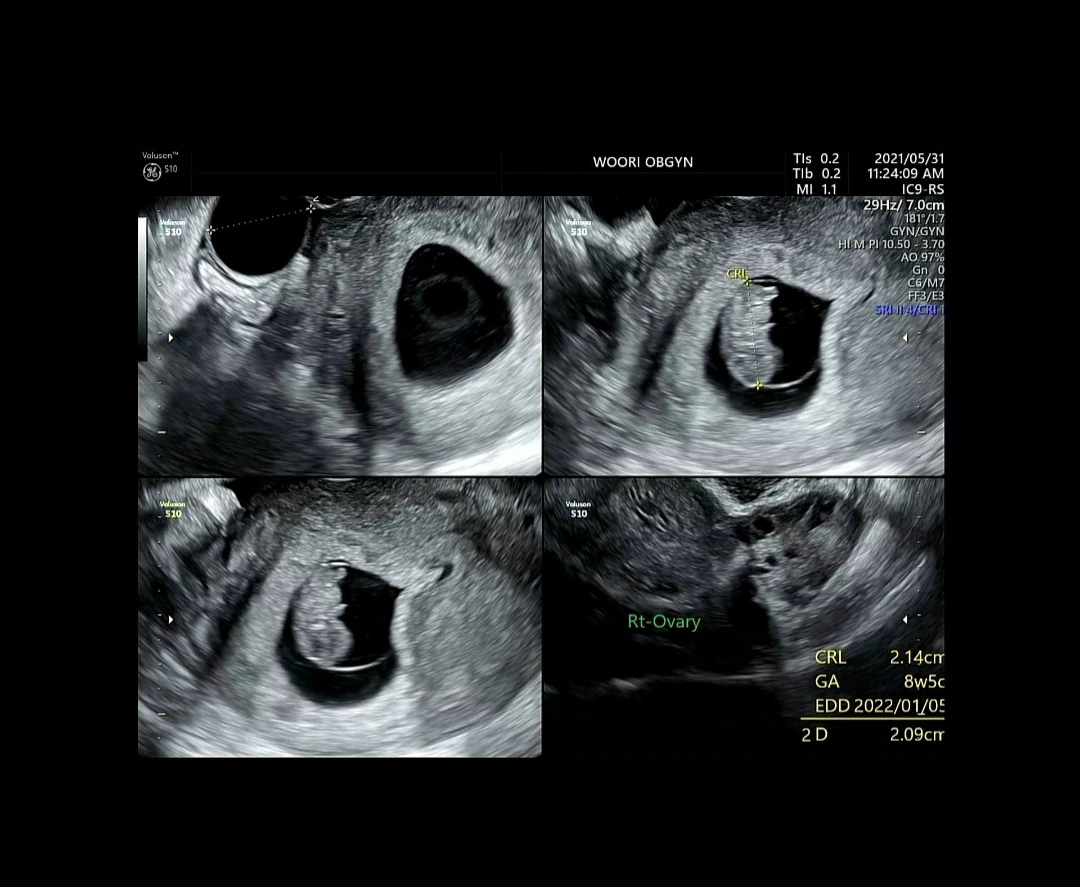

들어서자마자 의사 선생님은 ‘넘어지셨다면서요! 얼른 아가 보러 가시죠.’ 하고 나를 재촉했다.

간호사 선생님의 안내를 받아 초음파실로 들어갔다. 이제는 익숙한 듯 침대에 누워 배를 들어냈다.

약을 찌익 뿌려주시자마자 의사 선생님이 들어오셨다.

들어오셔서 초음파 기계를 내 배에 차갑게 댔다.

그 시간이 길지 않았다. 아주 짧은 시간이었다. 1분도 안 걸리는 아주 짧고 짧은 시간. 그런데 내가 잘못한 이후에 아가를 확인하는 시간이라 그런지 고작 1분이 나에게 한나절과 같았다. 얼른 아가를 확인하고 싶었다.

“아! 우리 아가 잘 있네요. 산모님!”

“아 정말요? 어디 크게 부딪힌 건 아닌데 너무 불안해서요. 쿵 소리가 나게 넘어졌거든요.”

“네네 괜찮아요. 우리 아가. 우리 아가들은 양수와 자궁에 안전하게 있거든요. 교통사고가 나거나 심하게 부딪힌 게 아니라면 양수와 자궁이 우리 아이를 잘 보호해 줄 거예요.”

“아. 다행이에요.”

아가는 다행히 씩씩하게 잘 있었다. 꼬꼬마 우리아가